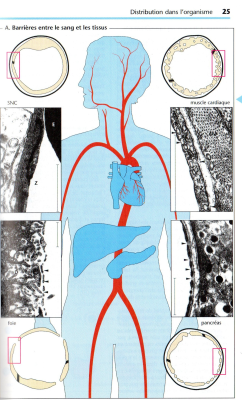

• barrières entre le sang et les tissus à franchir lors de  labsorption et la distribution et lélimination.jpg

• barrières entre le sang et les tissus à franchir lors de  labsorption et la distribution et lélimination (2).jpg

• distribution du médicament dans les differents tissus de lorganisme.jpg